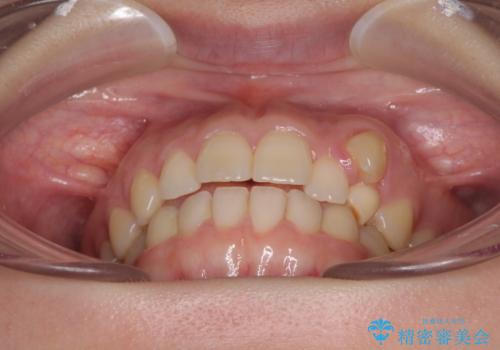

気になる残存乳歯と八重歯 ワイヤー矯正を併用したインビザライン治療

- 八重歯を気にして来院された患者様です。

八重歯のために乳歯が残存していたため、乳歯を抜去して八重歯となっている犬歯を歯列に収めることとしました。

八重歯の移動量が多くなるため、インビザラインと併用してワイヤー矯正を行い、八重歯を改善した後に、上下歯列をインビザラインで整えることとしました。

犬歯は歯根が長くて太いため移動に時間がかかる上に、周囲の歯が八重歯に寄ってきてしまうため、仕上がるまでに期間がかかりました。